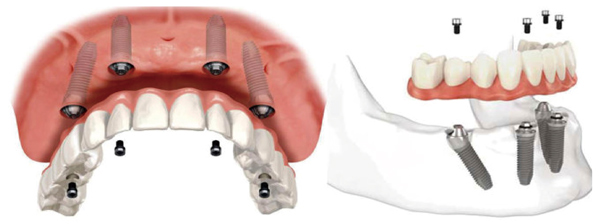

但是半口缺牙却可以在只种植4颗种植体的情况下,当天就戴整排牙冠,恢复咀嚼吃东西。这要仰赖1993年,牙医Paulo Malo和他的研究团队历时5年研究All-on-4种植牙。

顾名思义,All-on-4种植牙就是利用四个关键位置的种植体使牢固半口所有牙齿,并在当日戴牙。它的种植技术的核心在于两颗前牙部位的种植体垂直植入牙槽骨内,而两颗中远部位的种植体采取倾斜角度植入牙槽骨内,然后在种植体的基台上安装“拱形连桥”牙冠,这样整个种植牙的受力就呈现出“拱形”的特征,即一点受力会均匀地分布到整体,这在建筑学上是更为稳固的形状。这种稳固的结构也改善了在植入种植体的当天,就可以安装牙冠恢复美观和咀嚼。

▲All-on-4示意图